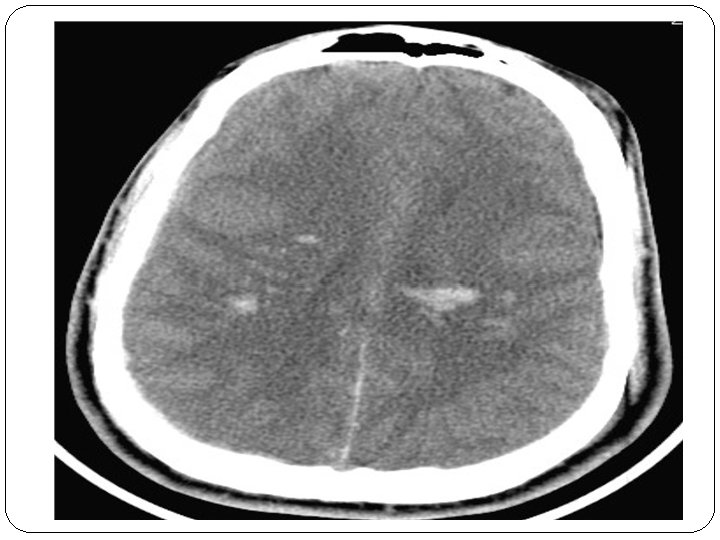

3 - PHYSIOPATHOLOGIE Les lésions peuvent être classées en lésions primaires et secondaires : Ø LES LÉSIONS PRIMAIRES inhérentes au traumatisme lui-même comprennent : * Les fractures du crâne * Les hématomes extra cérébraux, HSA * Les lésions intra parenchymateuses (contusions, lésions axonales diffuses). Ø LES LÉSIONS SECONDAIRES souvent plus dévastatrices que les atteintes primaires : * Engagements cérébraux et leurs complications vasculaires. * Œdème cérébral.

INDICATIONS NEUROCHIRURGICALES À LA PHASE PRÉCOCE Par contre, la gestion des lésions parenchymateuses (hématome, contusion) est souvent discutée, au cas par cas, en fonction de leur localisation, de leur taille et de leur implication dans l’hypertension intracrânienne. La plupart des équipes adoptent une attitude conservatrice sauf dans trois situations bien définies : – un hématome intracérébral ou une contusion hémorragique, d’un volume supérieur à 15 ml, avec déplacement de la ligne médiane supérieur à 5 mm et oblitération des citernes de la base, doit être évacué le plus précocement possible; – l’existence d’une anisocorie associée à une contusion temporale est une indication à faire une lobectomie temporale polaire; – devant la présence d’une contusion frontale unilatérale associée à une HIC non contrôlée malgré un traitement antiœdémateux adéquat il est nécessaire de discuter une lobectomie frontale. La craniotomie décompressive sera envisagée plus loin, dans le